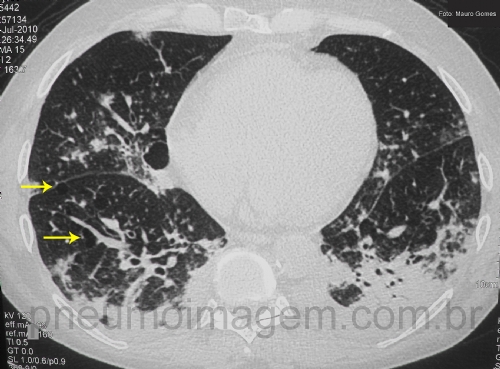

Veja imagens de PAC por Staphylococcus aureus no PneumoImagem, clique aqui.